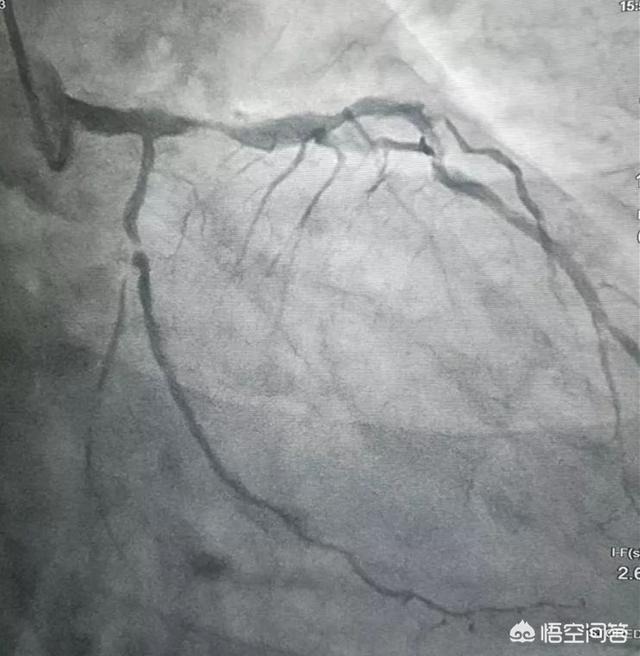

Un stent cardiaque, également appelé stent coronaire, est un dispositif utilisé dans la procédure d'angioplastie coronaire transluminale percutanée (ACTP). Les stents cardiaques ressemblent à de minuscules tubes métalliques à paroi maillée situés à l'extérieur du corps et sont constitués de fils et de microcapsules à l'avant des fils, etc. Les stents artériels peuvent jouer un rôle permanent en soutenant les artères, en résolvant les sténoses et en assurant une circulation sanguine fluide. Ils sont généralement utilisés dans le traitement de l'infarctus aigu du myocarde et d'autres syndromes coronariens aigus afin de sauver la vie du patient ou d'améliorer sa qualité de vie.

La chirurgie du stent cardiaque consiste d'abord à ouvrir une petite ouverture dans l'artère du bras ou de la jambe d'une personne, puis à insérer dans la ligne une sonde chargée d'une petite balle qui, grâce à l'observation par ultrasons de la petite balle, atteint les vaisseaux sanguins de l'artère coronaire à l'endroit de l'obstruction, après l'ouverture de la balle, qui est un parapluie de fer.